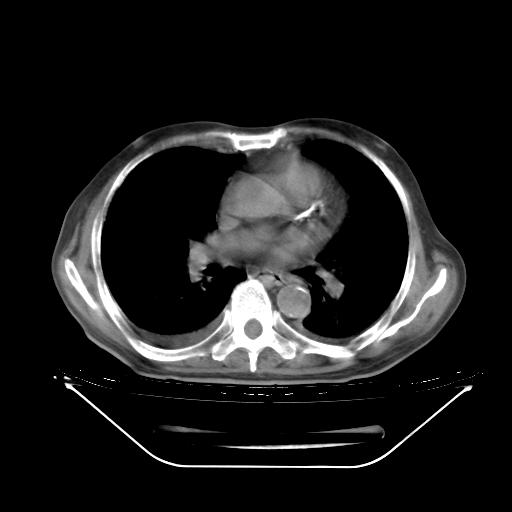

胸腹部CT,诊断意见:左上肺叶钙化灶、左侧胸膜局限性增厚并钙化、胆囊炎。描述部分肺组织呈磨玻璃样改变。

今天复查肺部CT,发现双肺广泛磨玻璃样改变。所以我把3月19日和5月9日相隔50天的肺部CT上传。请大家会诊。

2009年3月19日肺部CT片。

大致读了系列胸部CT:纵隔窗无明显异常,肺窗:从4、27至今:主要是双肺中下野外带可见毛玻璃样改变,目前处于急性肺泡炎阶段,至于原因考虑1、结替组织或胶原血管性疾病所致?2、恶性疾病如恶组在肺部所致的表现或细支气管肺泡癌?3、药物或其它原因如肺蛋白沉着症所致肺泡炎目前不太可能?总之,明天就去请我院的呼吸科、感染科、血液科和临免专家会诊哈。